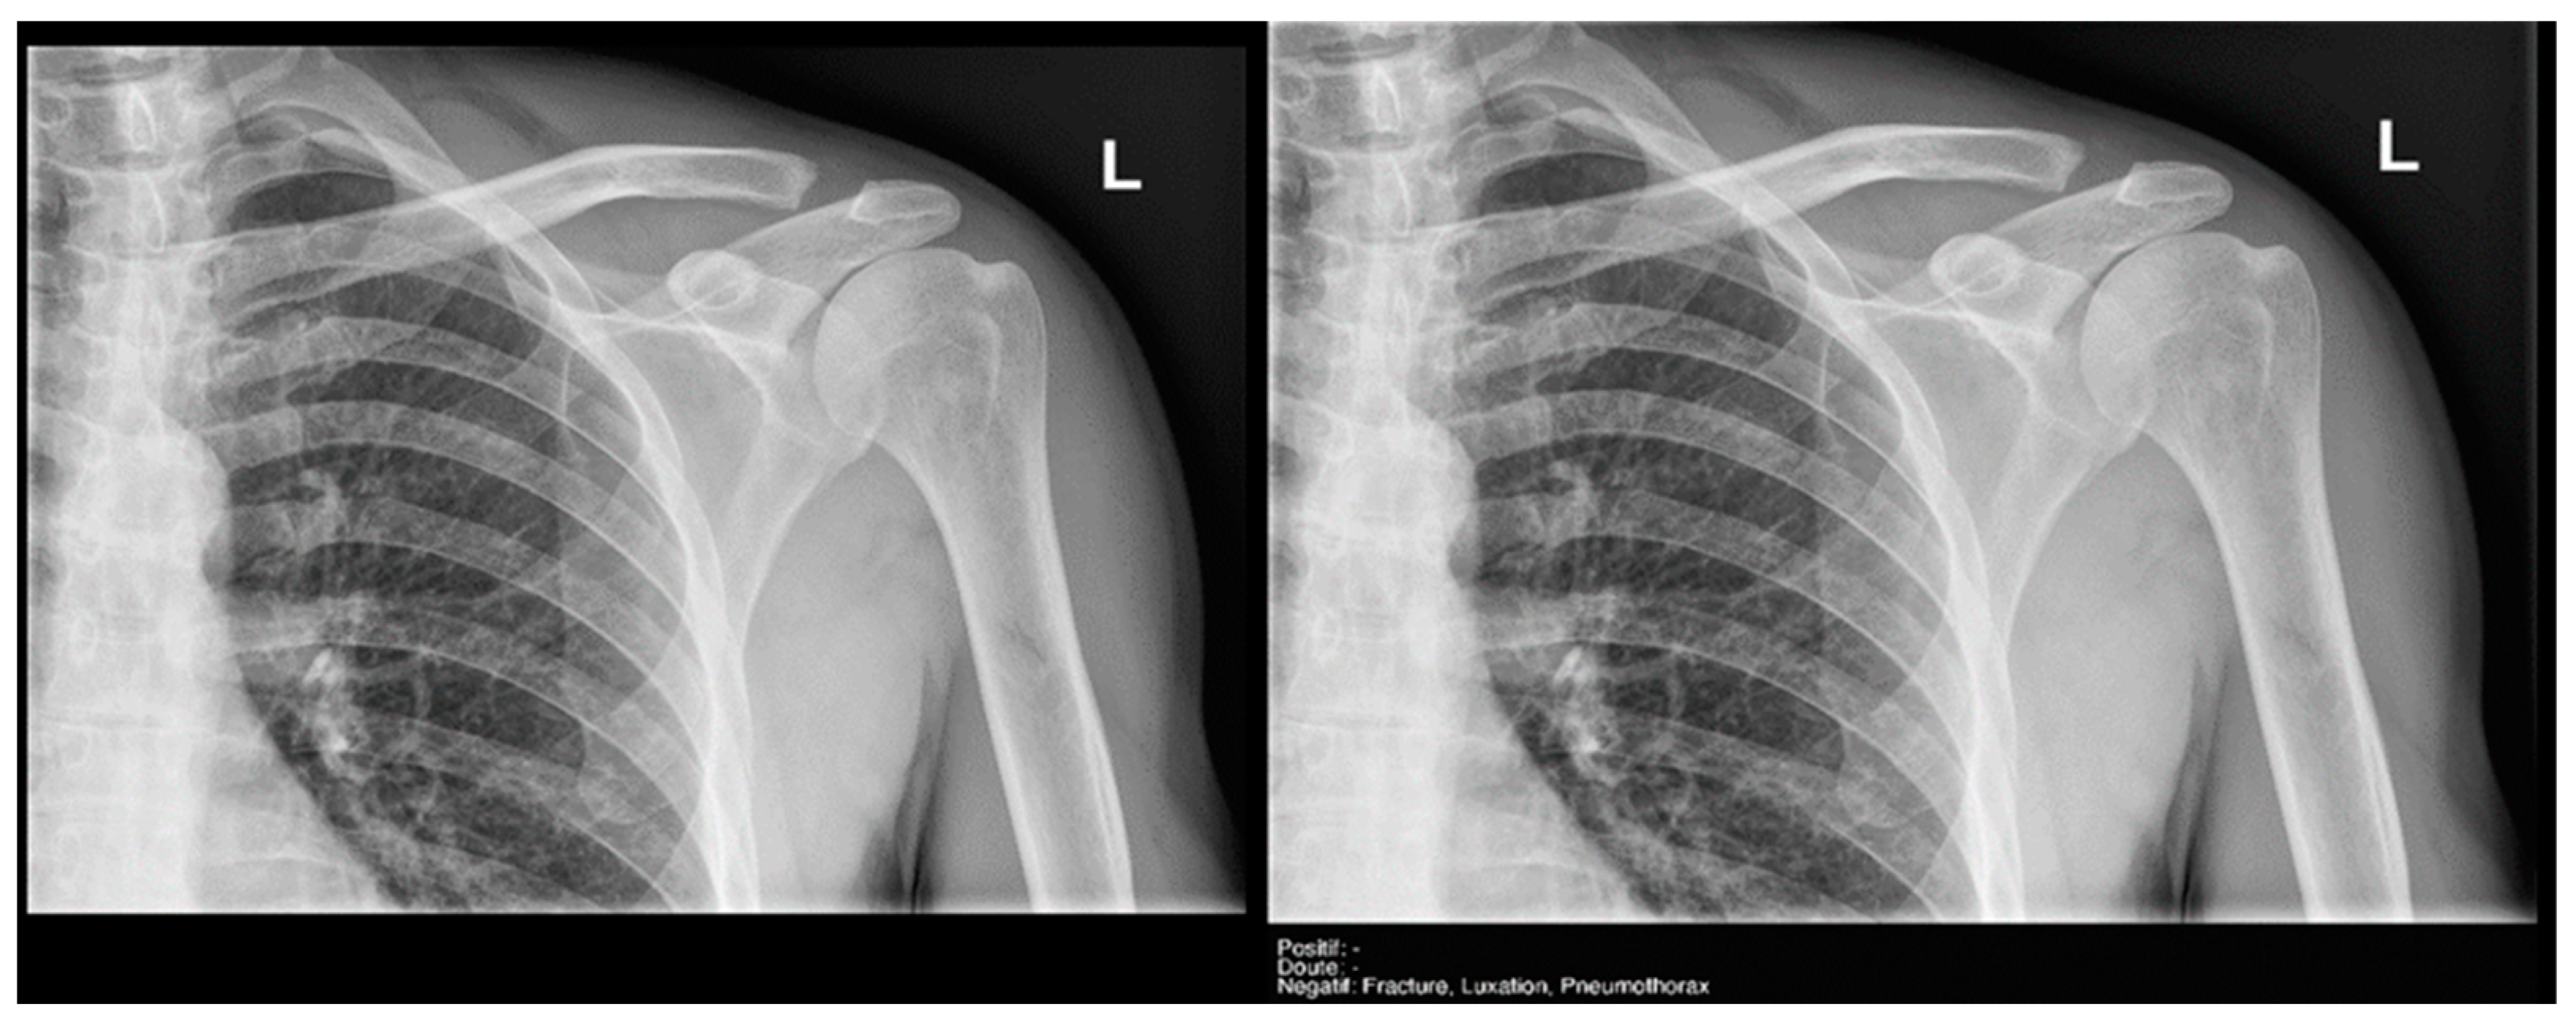

Finally, the specific case of acromioclavicular dislocations is particularly striking, as none of the cases were reported as positive or doubtful by Milvue (Figure 11). We have also not found studies that evaluate the diagnostic capacity of AI in detecting acromioclavicular dislocations. This leads us to propose that future updates of the AI system should focus on expanding the training dataset to include a larger sample of acromioclavicular joint cases, particularly those with pathological conditions, in order to improve the system’s ability to accurately detect these dislocations.

Figure 11.

Acromioclavicular joint dislocation recorded as negative by AI and positive by radiology resident.